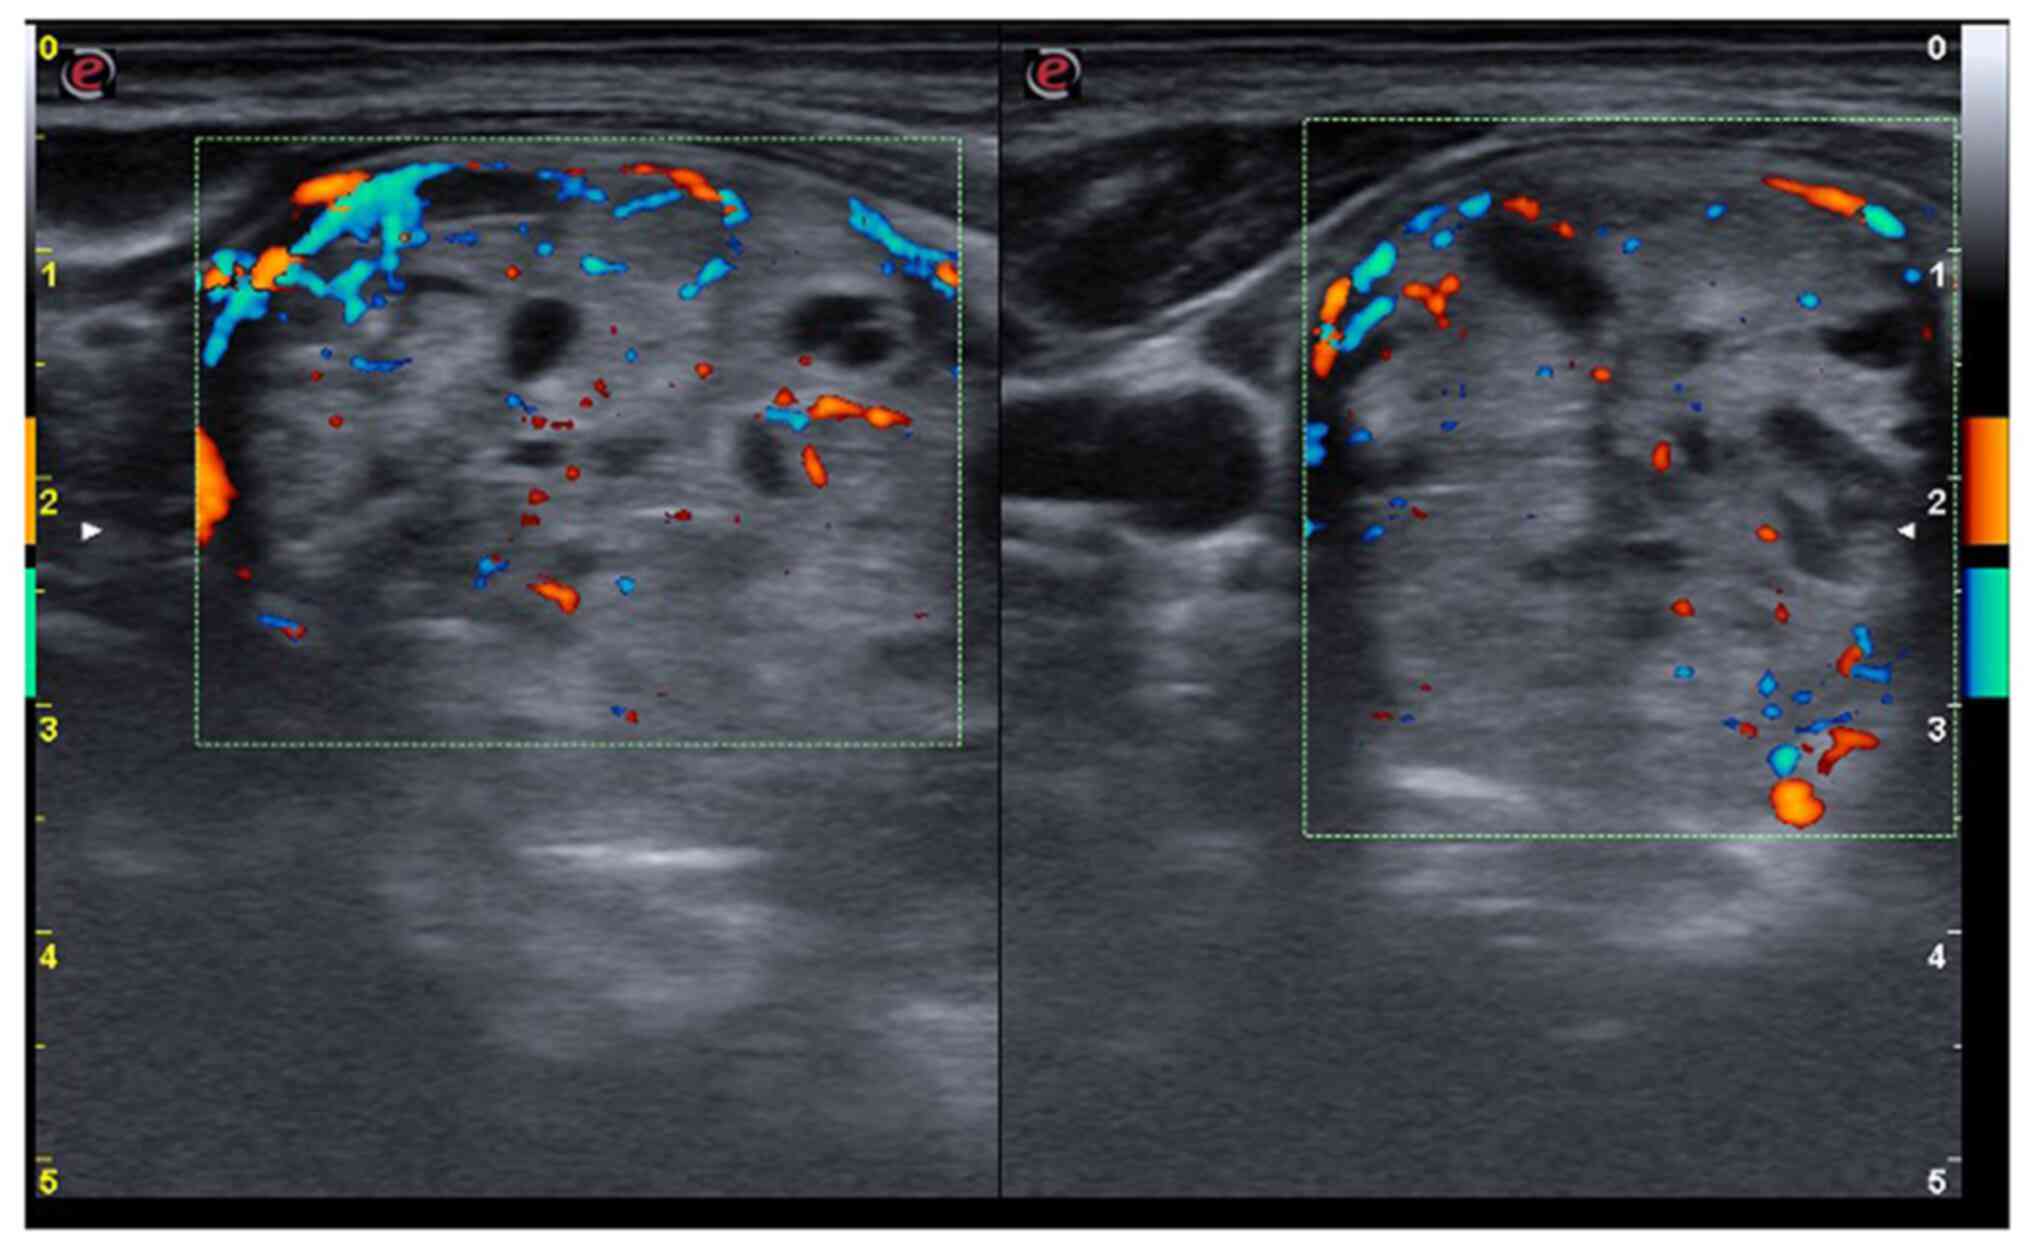

The neck ultrasound detected a hypoechoic thyroid parenchyma with an increased volume of the thyroid (26.8 ml, upper normal limit <16 ml). The right lobe was completely replaced by a spongiform nodule, with increased vascularity (Fig. 1), which was classified as benign by ACR-TIRADS (score 2) (15). The left lobe exhibited increased vascularity and, close to the posterior capsule, there was a partially cystic nodule of 6/5/7 mm (Fig. 2), also classified as benign by ACR-TIRADS (score 2).

Figure 1

Right thyroid lobe is replaced by a spongiform nodule (transverse plane).

Figure 2

Increased vascularity in the left thyroid lobe and a solid nodule near the posterior capsule (transverse plane).